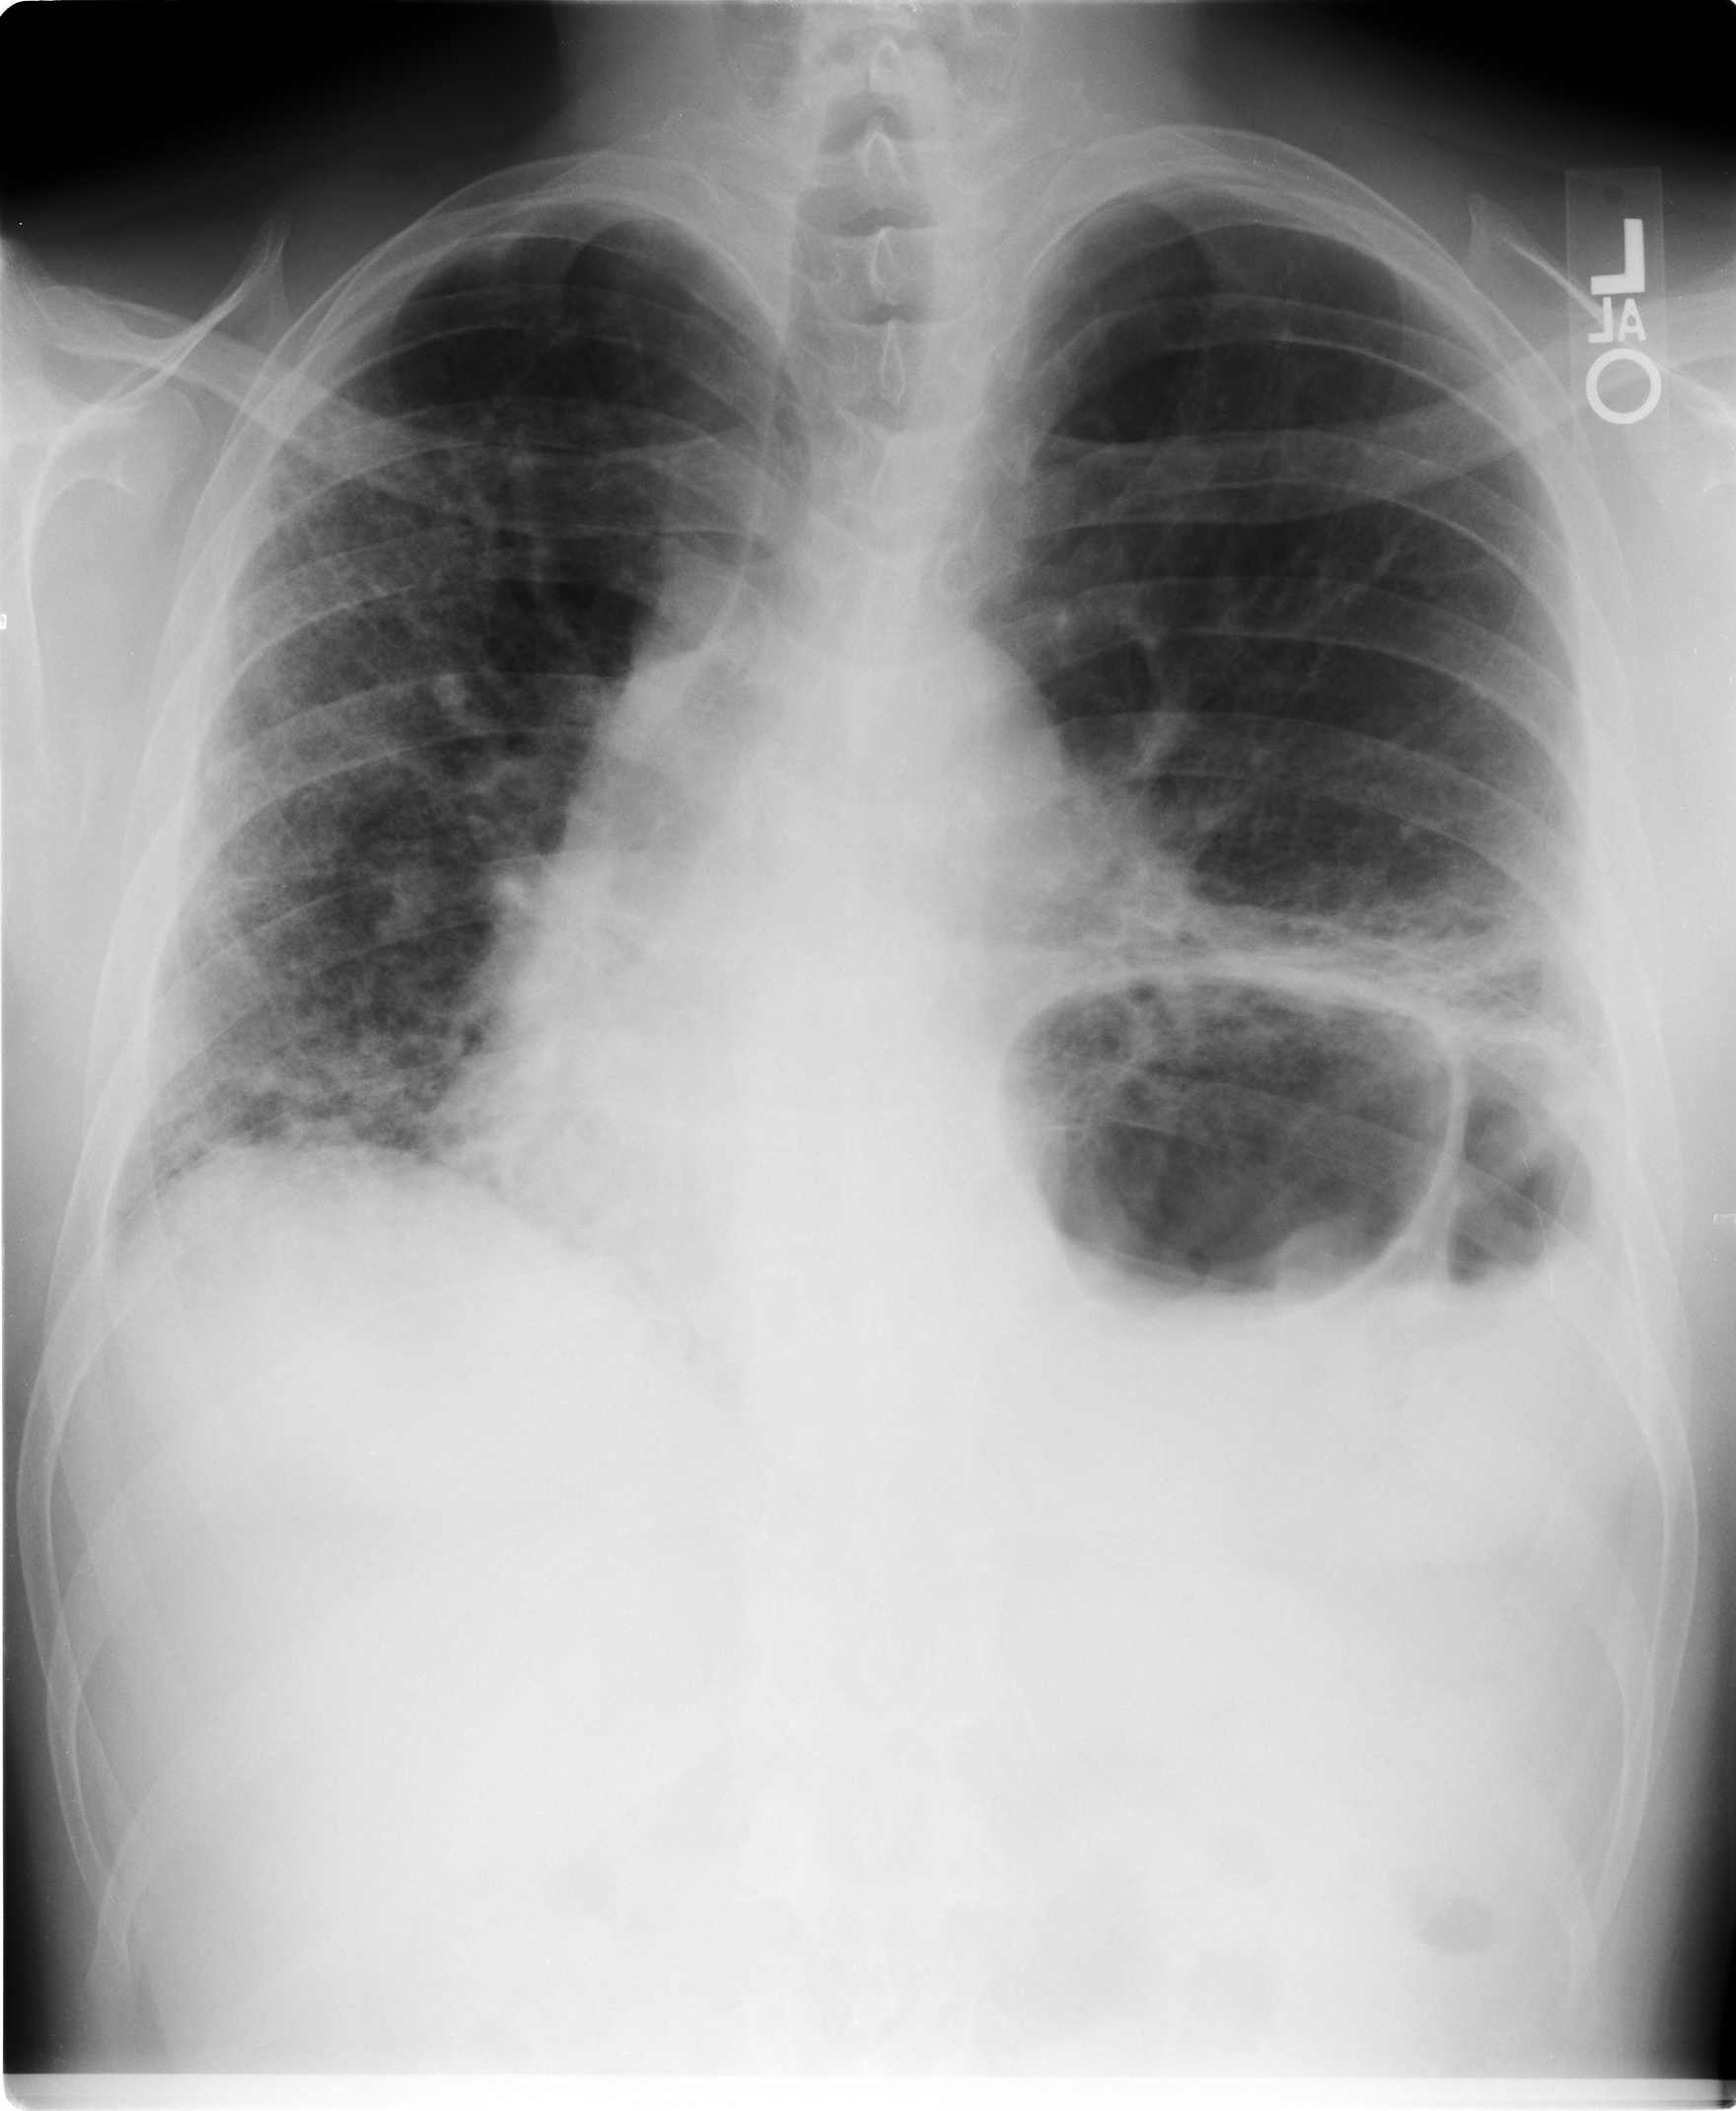

After several months of symptoms unresponsive to antibiotics, a chest radiograph was performed and revealed interstitial disease. He was subsequently referred to a pulmonologist who performed pulmonary function tests that showed restriction and a severely reduced diffusion capacity.

A high-resolution computed tomography (HRCT) of the chest showed diffuse ground-glass opacities with bibasilar fibrotic changes. A bronchoscopy with bronchoalveolar lavage and transbronchial biopsy revealed 30% lymphocytes and nondiagnostic pathology. An open lung biopsy revealed fibrotic nonspecific interstitial pneumonia (NSIP). Prednisone was started with some initial symptomatic improvement. His symptoms, however, progressed again despite continued prednisone, and he was referred to our institution for a second opinion. At the time we evaluated him, his symptoms were present 1 year and had continued to progress despite the treatment with prednisone. His physical examination revealed diffuse inspiratory crackles and he required continuous supplemental oxygen because of resting hypoxemia.